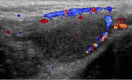

Testicular ischemia is a rare complication of inguinal hernia repair. It results from the injury to the vessels that course along the inguinal canal. Typically it is painful at the beginning and asymptomatic later. Ultrasonographic appearance and aspects of testicular ischemia result in diffusely hypoechoic and disomogeneous testis, with complete lack of intratesticular vascular signal on color-Doppler and cremasteric vessels hypertrophy in chronic cases.This report describes a testicular ischemia seen in a patient referred to because of hernia recurrence, without any sign or symptom of acute scrotum. Ultrasound examination showed the most frequent complications after inguinal hernia repair: both hernia recurrence and testicular ischemia.